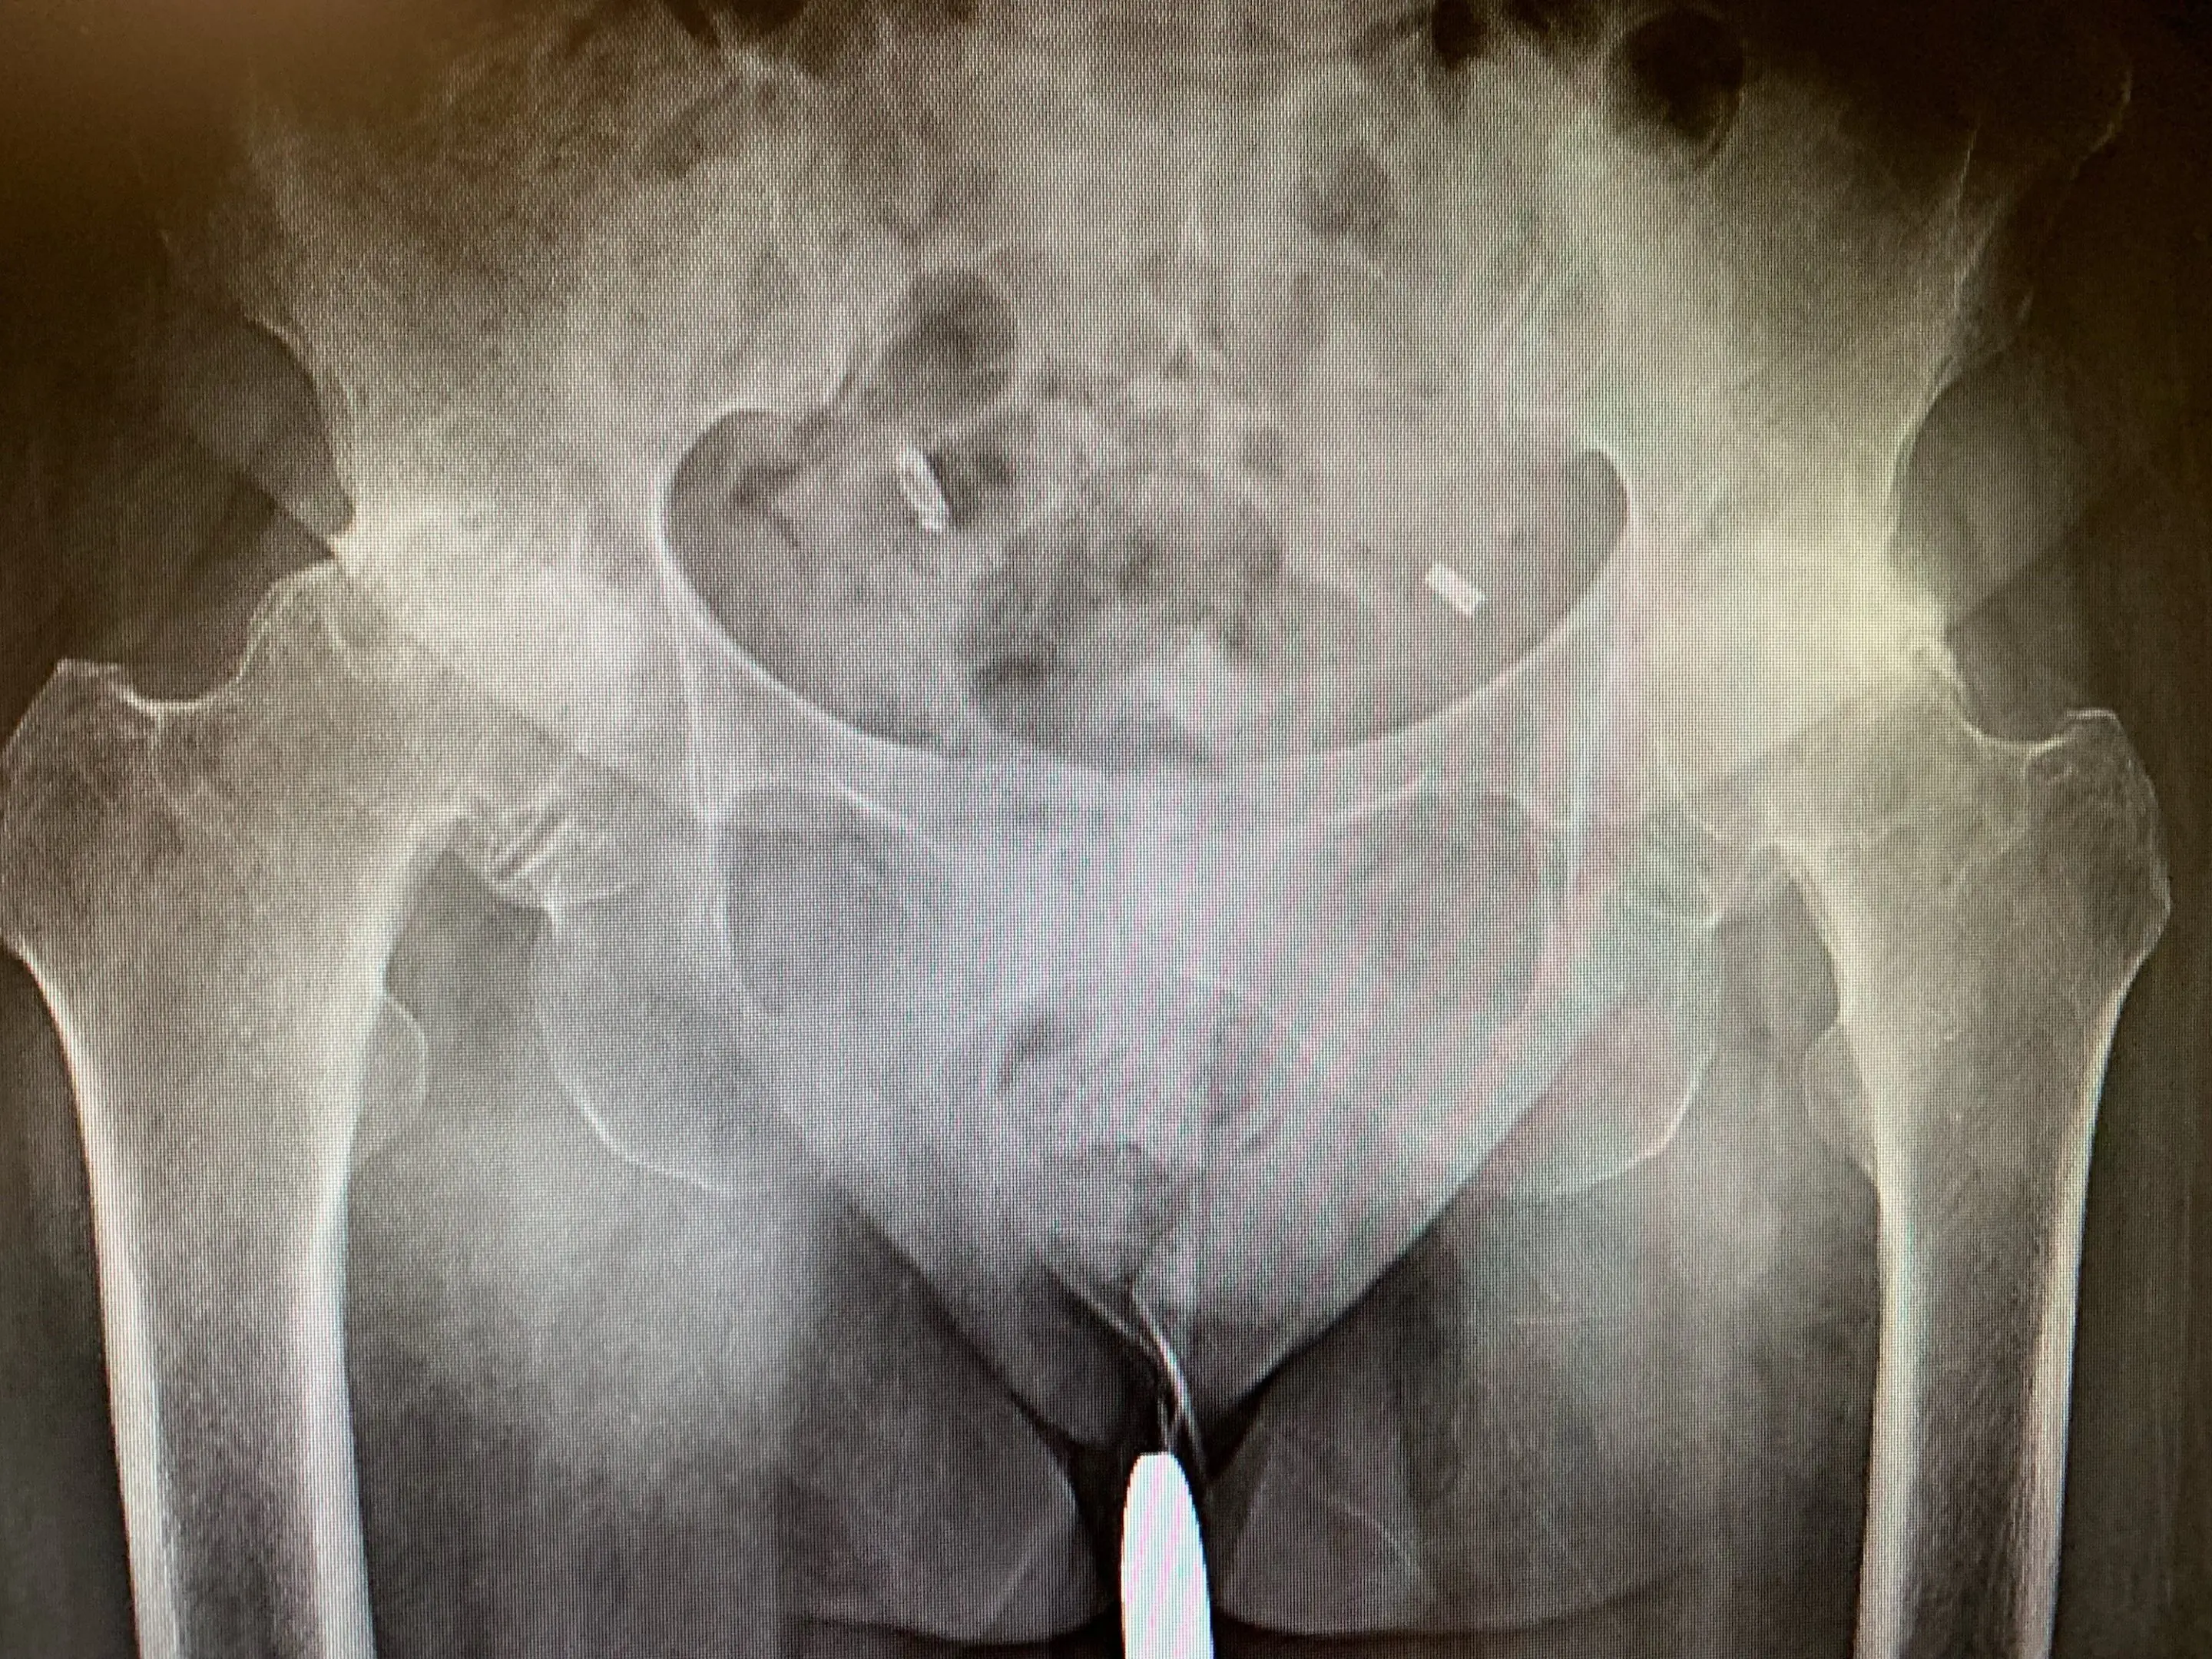

Full assessment of Mrs. CM including examination and radiographs revealed bilateral hip osteoarthritis of moderate severity. Her hip examination was unremarkable, with a remarkably good range of motion considering the level of arthritis she suffered from.

Pre-op